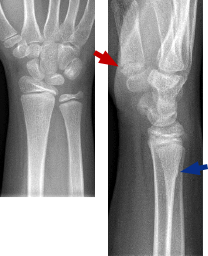

Occasionally, a buckle is seen, but on closer inspection, the X-ray reveals a more significant fracture type. If a greater force is applied to the volar side (ie, fall at greater speed or from height, like monkey bars), then a more significant fracture may occur, one that extends across both the dorsal and volar cortices (see Case 1). In some cases, the fracture line may not clearly extend to the volar side, but the distal fragment is mildly angulated dorsally (see Case 3). These are not simple dorsal buckle fractures. They are transverse fractures (complete or bicortical).

Finally, the last case (Case 4) involves the most common ED molding mistake seen in our fracture clinic: failure to recognize the volar buckle fracture. In these cases, the distal radius fracture tends to shift volarly. A helpful tip: When looking at the lateral wrist X-ray, always identify the thumb first as this defines the volar side of the forearm. If a buckle is seen on the volar cortex, the force must have come in the dorsal-to-volar direction, and when asked, patients often report a fall on the back of their hand, not on their outstretched arm. If such fractures shift, they shift volarly, so molding must be in the opposite direction in extension.

Patient 1: 14-year-old male

Patient 3: 7-year-old male